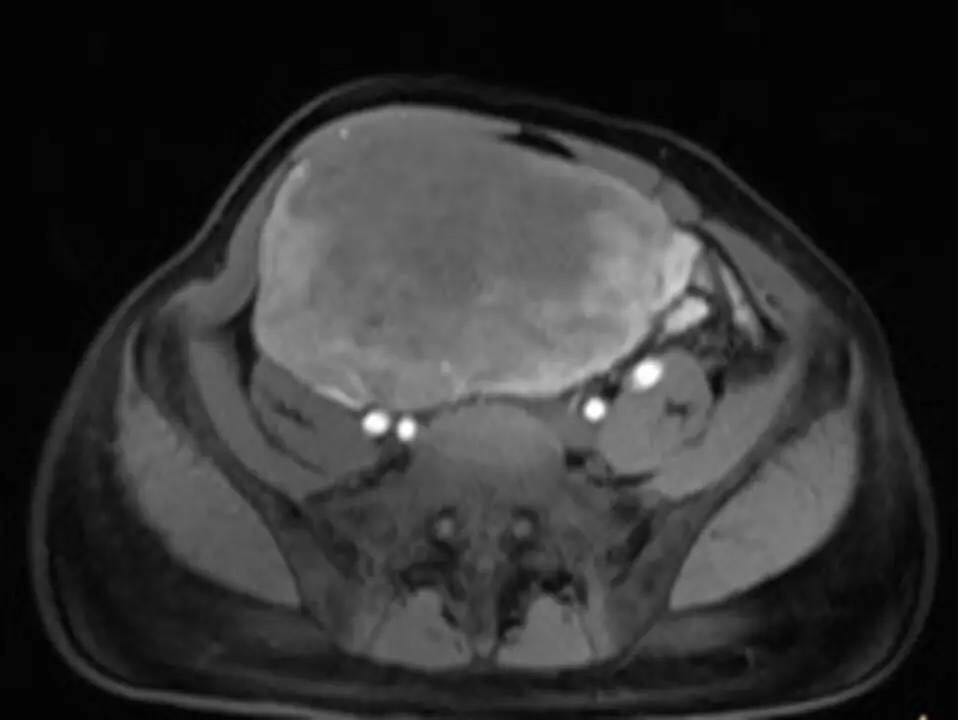

MRI表现,腹盆腔见不均质肿块,与肌肉相比为等低密度,强化不明显。T1WI信号均匀,T2WI高低混杂信号,增强后渐进性强化,病变各序列可见斑片状低信号区。 诊断,腹腔侵袭性纤维瘤病。

AF的影像学表现具有一定特征性。影像上表现为边界欠清的软组织肿块,钙化、出血少见,即便在较大的肿瘤中也看不到中央性坏死。病灶CT密度欠均匀,与邻近骨骼肌相近,强化不明显。T1WI信号基本均匀,明显或中度强化,典型强化方式呈渐进性。所有序列中都可以看到一定的低信号区,在病理上相对应的为病变内胶原纤维丰富的区域,此区域强化较轻。 侵袭性纤维瘤病虽然少见,但是平常工作中需要考虑到侵袭性纤维瘤病的诊断,尤其是中年女性腹腔的肿块。MRI为最佳的检查方法,可以显示一定的影像学特征。